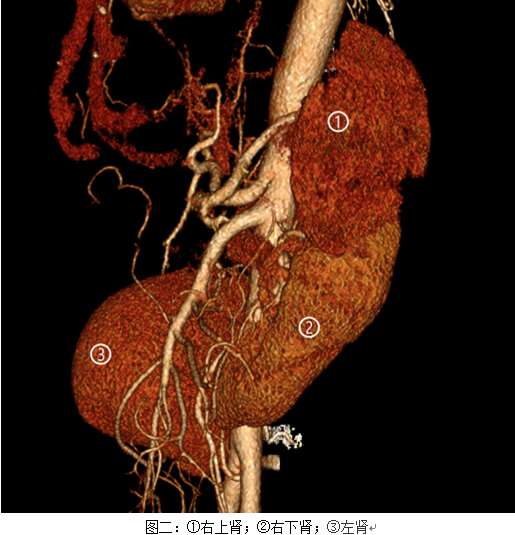

马蹄肾是泌尿系统少见的先天性畸形之一, 是指两侧肾的上极或下极在脊柱大血管前相互融合在一起,形成“马蹄铁”形的先天性畸形。在人群中的发病率是1:500,而马蹄肾合并重复肾更是罕见,国内外文献报道极少。患者病情复杂,治疗尤其困难,故将患者病情提请全科讨论。姜庆主任高度重视,亲自主持全科讨论。全科医生讨论后决定先继续完善肾显象、肾动脉CTA及三维重建等检查。CTA提示右下肾无血供、无功能;右上肾血供基本正常,左肾血供基本正常。CTA图像(图二)更是让所有人大吃一惊,从三维重建上看三个肾连到了一起,而中间那个肾没有功能、重度积水,需要切除。终于诊断明确,但更困难的是如何治疗。